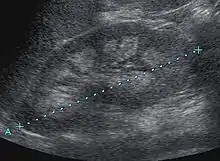

Nephrocalcinosis is diagnosed for the most part by imaging techniques. The imagings used are ultrasound (US), abdominal plain film and CT imaging.[10] Of the 3 techniques CT and US are the more preferred. Nephrocalcinosis is considered present if at least two radiologists make the diagnosis on US and/or CT. In some cases a renal biopsy is done instead if imaging is not enough to confirm nephrocalcinosis. Once the diagnosis is confirmed additional testing is needed to find the underlying cause because the underlying condition may require treatment for reasons independent of nephrocalcinosis.[10] These additional tests will measure serum, electrolytes, calcium, and phosphate, and the urine pH.[10] If no underlying cause can be found then urine collection should be done for 24 hours and measurements of the excretion of calcium, phosphate, oxalate, citrate, and creatinine are looked at.[10]